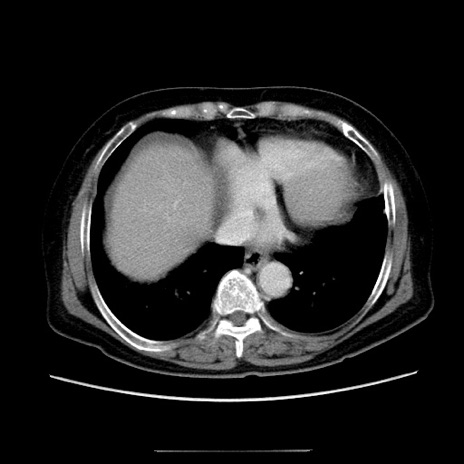

冠状断像

【症例】70歳代女性

【主訴】お腹が張る

【現病歴】1週間くらい前から腹部膨満の自覚あり。昨日夜から増悪したため、本日救急外来受診。

【身体所見】意識清明、BT 36.5℃、BP 165/106mmHg、HR 80bpm、SpO2 98%、腹部:膨満、軟、自発痛・圧痛なし、触診にて不快感あり、腸蠕動音:減弱

【データ】WBC 12600、CRP 1.04